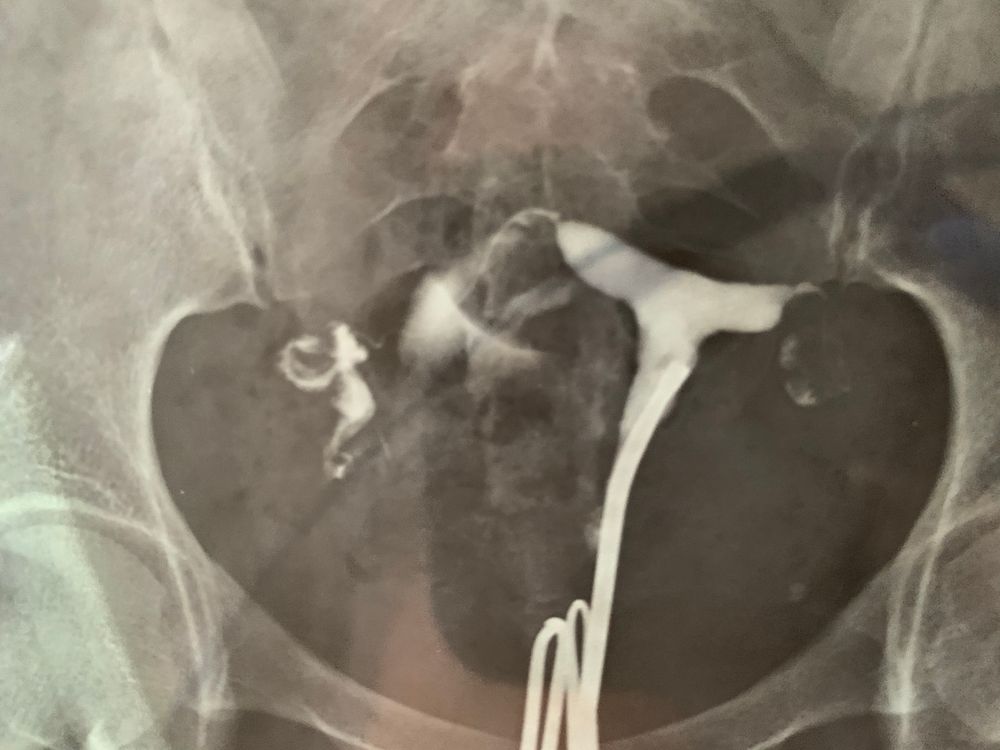

Гистеросальпингография: описание и фотографии